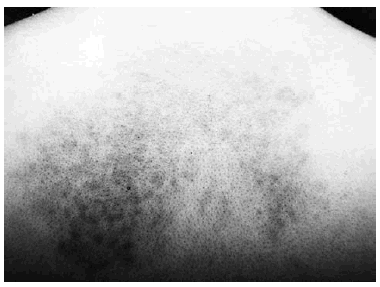

Presentaba una mácula hiperpigmentada de coloración azul-violácea y aspecto moteado que abarcaba la región interescapular. La lesión tenía unos bordes uniformes y bien delimitados (fig. 1). El resto de la exploración dermatológica no ofrecía ninguna otra lesión de interés. Se procedió a la realización de una biopsia cutánea que reveló una epidermis y una dermis normales salvo por la presencia en dermis reticular de células ovaladas, fusiformes y alargadas con intensa pigmentación melánica y algunas ramificaciones (figs. 2 y 3). Se efectuó una tinción con rojo Congo que resultó negativa. Las tinciones inmunohistoquímicas para proteína S100 y HMB 45 demostraron positividad de esas células. En la microscopia electrónica se pudo confirmar la presencia de melanocitos dérmicos. Debido a las dificultades para desparafinar la pieza no fue posible determinar la presencia de vaina extracelular melanocítica debido a la deficiente calidad de las imágenes.

Fig. 3. Detalle de los melanocitos dérmicos.

Los melanocitos dérmicos suelen presentar una morfología diferente a los melanocitos localizados en la epidermis, presentando unos citoplasmas alargados y ramificados intensamente pigmentados. Ultraestructuralmente, el melanocito dérmico se caracteriza por la presencia de melanosomas libres, pequeñas gotas lipídicas intracitoplasmáticas y la existencia de una característica vaina extracelular.